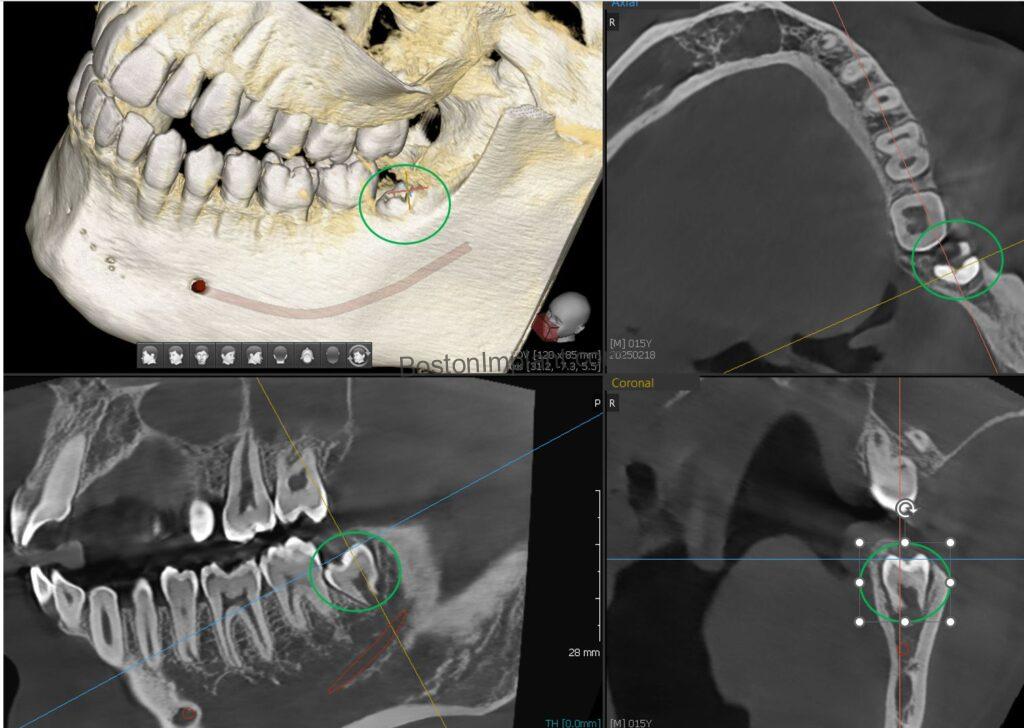

5. Wisdom Teeth Assessment: Many wisdom teeth are impacted, and it’s often difficult to predict their exact shape and their relationship to the inferior alveolar nerve using traditional x-rays. Three-dimensional CBCT imaging provides the surgeon with the precise relationship, leading to more accurate diagnoses and safer treatment.